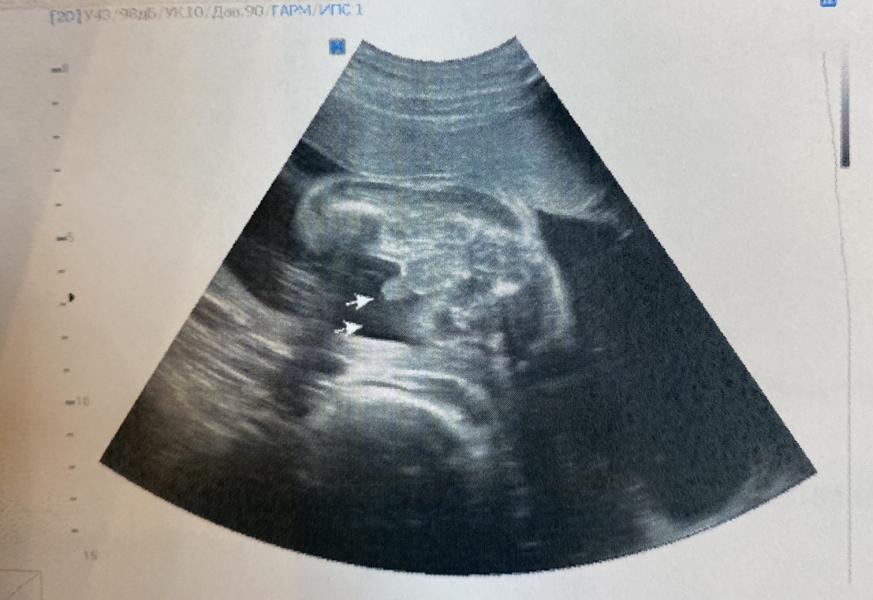

Приложу фото, наконец - то мне показали, что у меня сын 🤣

Напомню, что на 15 неделе я сдала кровь на определение пола ребёнка) но потом на узи говорили, что у меня девочка, на втором скрининге бесплатном, врач была не многословна, просто буркнула под нос себе, что пол ребёнка мальчик, но ничего не показала, а так хотелось.